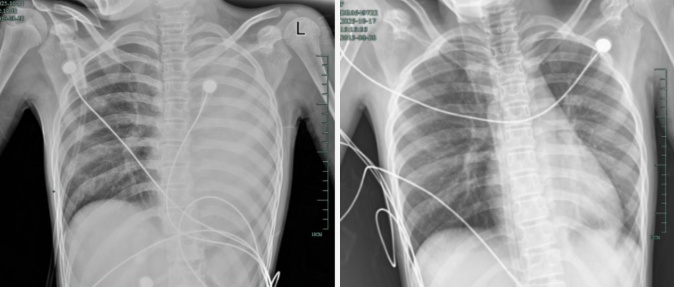

治療前后影響對(duì)比,左肺從“白肺”到正常狀態(tài)

呼吸急促、胸悶胸痛,體溫38.5℃,只能靠 5L/min 的面罩吸氧維持血氧,胸片顯示左肺已完全呈 “白肺” 改變,肺部炎癥進(jìn)展迅猛。